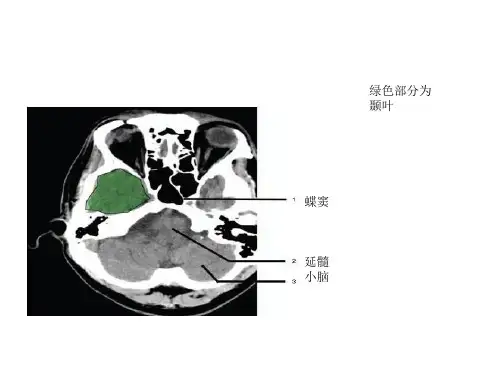

二、鞍上池层面

颅前窝:颞叶。

鞍上池:在垂体窝上方,位于两侧颅中窝之间,前界 为额叶直回,侧方为颞叶海马,呈五角星形或六角 行星。其前角连于纵裂池,两外侧角连于外侧裂池, 两后外侧角延续于环池,(第六个角(后面)位于 后缘中央,是角间池)。